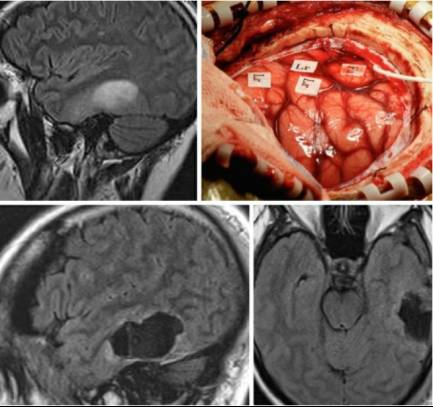

病例2:另一名年轻患者因癫痫就诊,后诊断为左侧颞叶肿瘤。

图11. 位于左侧颞叶语言皮层附近的低级别胶质瘤。肿瘤导致脑回轻微扩张,术中皮层定位标记了仅稍位于脑回前上方的语言(Lr)和面部(Fa)区域(上图)。在连续的术中监测下,肿瘤完全切除(下图)。

不论正被定位的区域是何种功能,笔者在术中均会频繁使用神经监测来指导手术切除方案。一旦有任何轻微的功能受损,笔者就会改变方案,并/或停止接下来的切除操作。